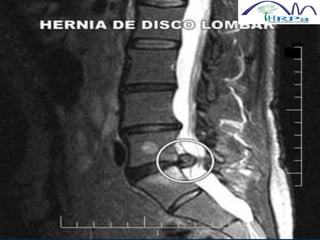

HÉRNIA LOMBAR

 Modic (1986) demonstra que a RNM apresenta a

melhor avaliação dignóstica do que a mielografia

e a TC